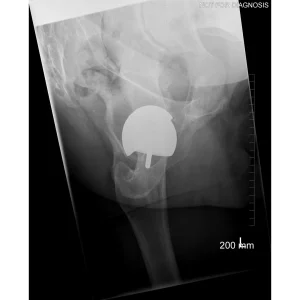

Hip resurfacing is a type of hip surgery used to treat hip arthritis, most commonly in younger and more active patients. Unlike a total hip replacement, hip resurfacing preserves more of your natural thigh bone. Instead of removing the entire femoral head (ball at the top of the thigh bone), the damaged surface is trimmed and covered with a smooth metal cap. The hip’s socket on the pelvis is also fitted with a metal cup.

Hip Resurfacing

- Preserves more natural bone (the femoral head is capped rather than replaced)

- Uses a larger ball size, which may reduce the risk of dislocation